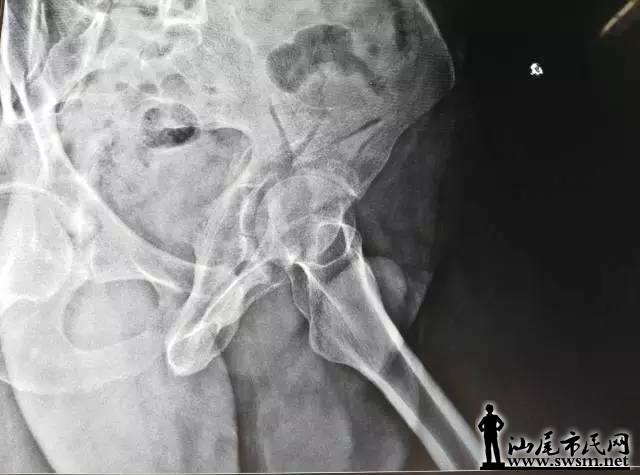

海丰县中医医院骨三科团队,利用3D打印技术,事先将患者的骨盆CT扫描数据输入电脑,再用先进的3D打印机,以1:1比例打印出熊先生的仿真骨盆模型。预先为其设计好最佳的手术治疗方案。                   640.webp.jpg                                                                          ( 上图:术前DR片)                                                                                                                   640.webp (1).jpg       640.webp (2).jpg                                                 (上图:术前CT片)

骨三科团队手术前在仿真骨盆进行虚拟手术,设计好钢板旋转的最佳位置、螺钉植入的最佳方向,并进行钢板、螺钉长度的数据测量,螺钉方向导航模块的设计及钢板预弯等一系列术前体外模拟手术,所有准备工作操练完毕,最后才正式为其施髋臼骨折复位钢板内固定手术。                                     640.webp (3).jpg                                                                                  (上图:虚拟手术,预弯钢板、测螺钉长度等数据)

由于钢板放置最佳位置、螺钉长度等已按照伤者的身体进行过精准的测量,减少了不必要的显露,手术切口仅8厘米;手术中也不需要反复预弯钢板和测定螺钉,使得手术时间大大减少。真正的内固定手术不到1小时,另外前后出血不足600毫升,大大节约血源、减少输血风险等,提高了手术的安全性,减少了伤者的痛苦。                                                                                        640.webp (4).jpg 640.webp (5).jpg 640.webp (6).jpg 640.webp (7).jpg                                                                          从术后复查钢板位置及螺钉植入方向、长度与术前3D打印模拟手术完全匹配,患者术后第二天便可以自行翻身、半坐等,良好的疗效受到了患者及其家属的称赞。